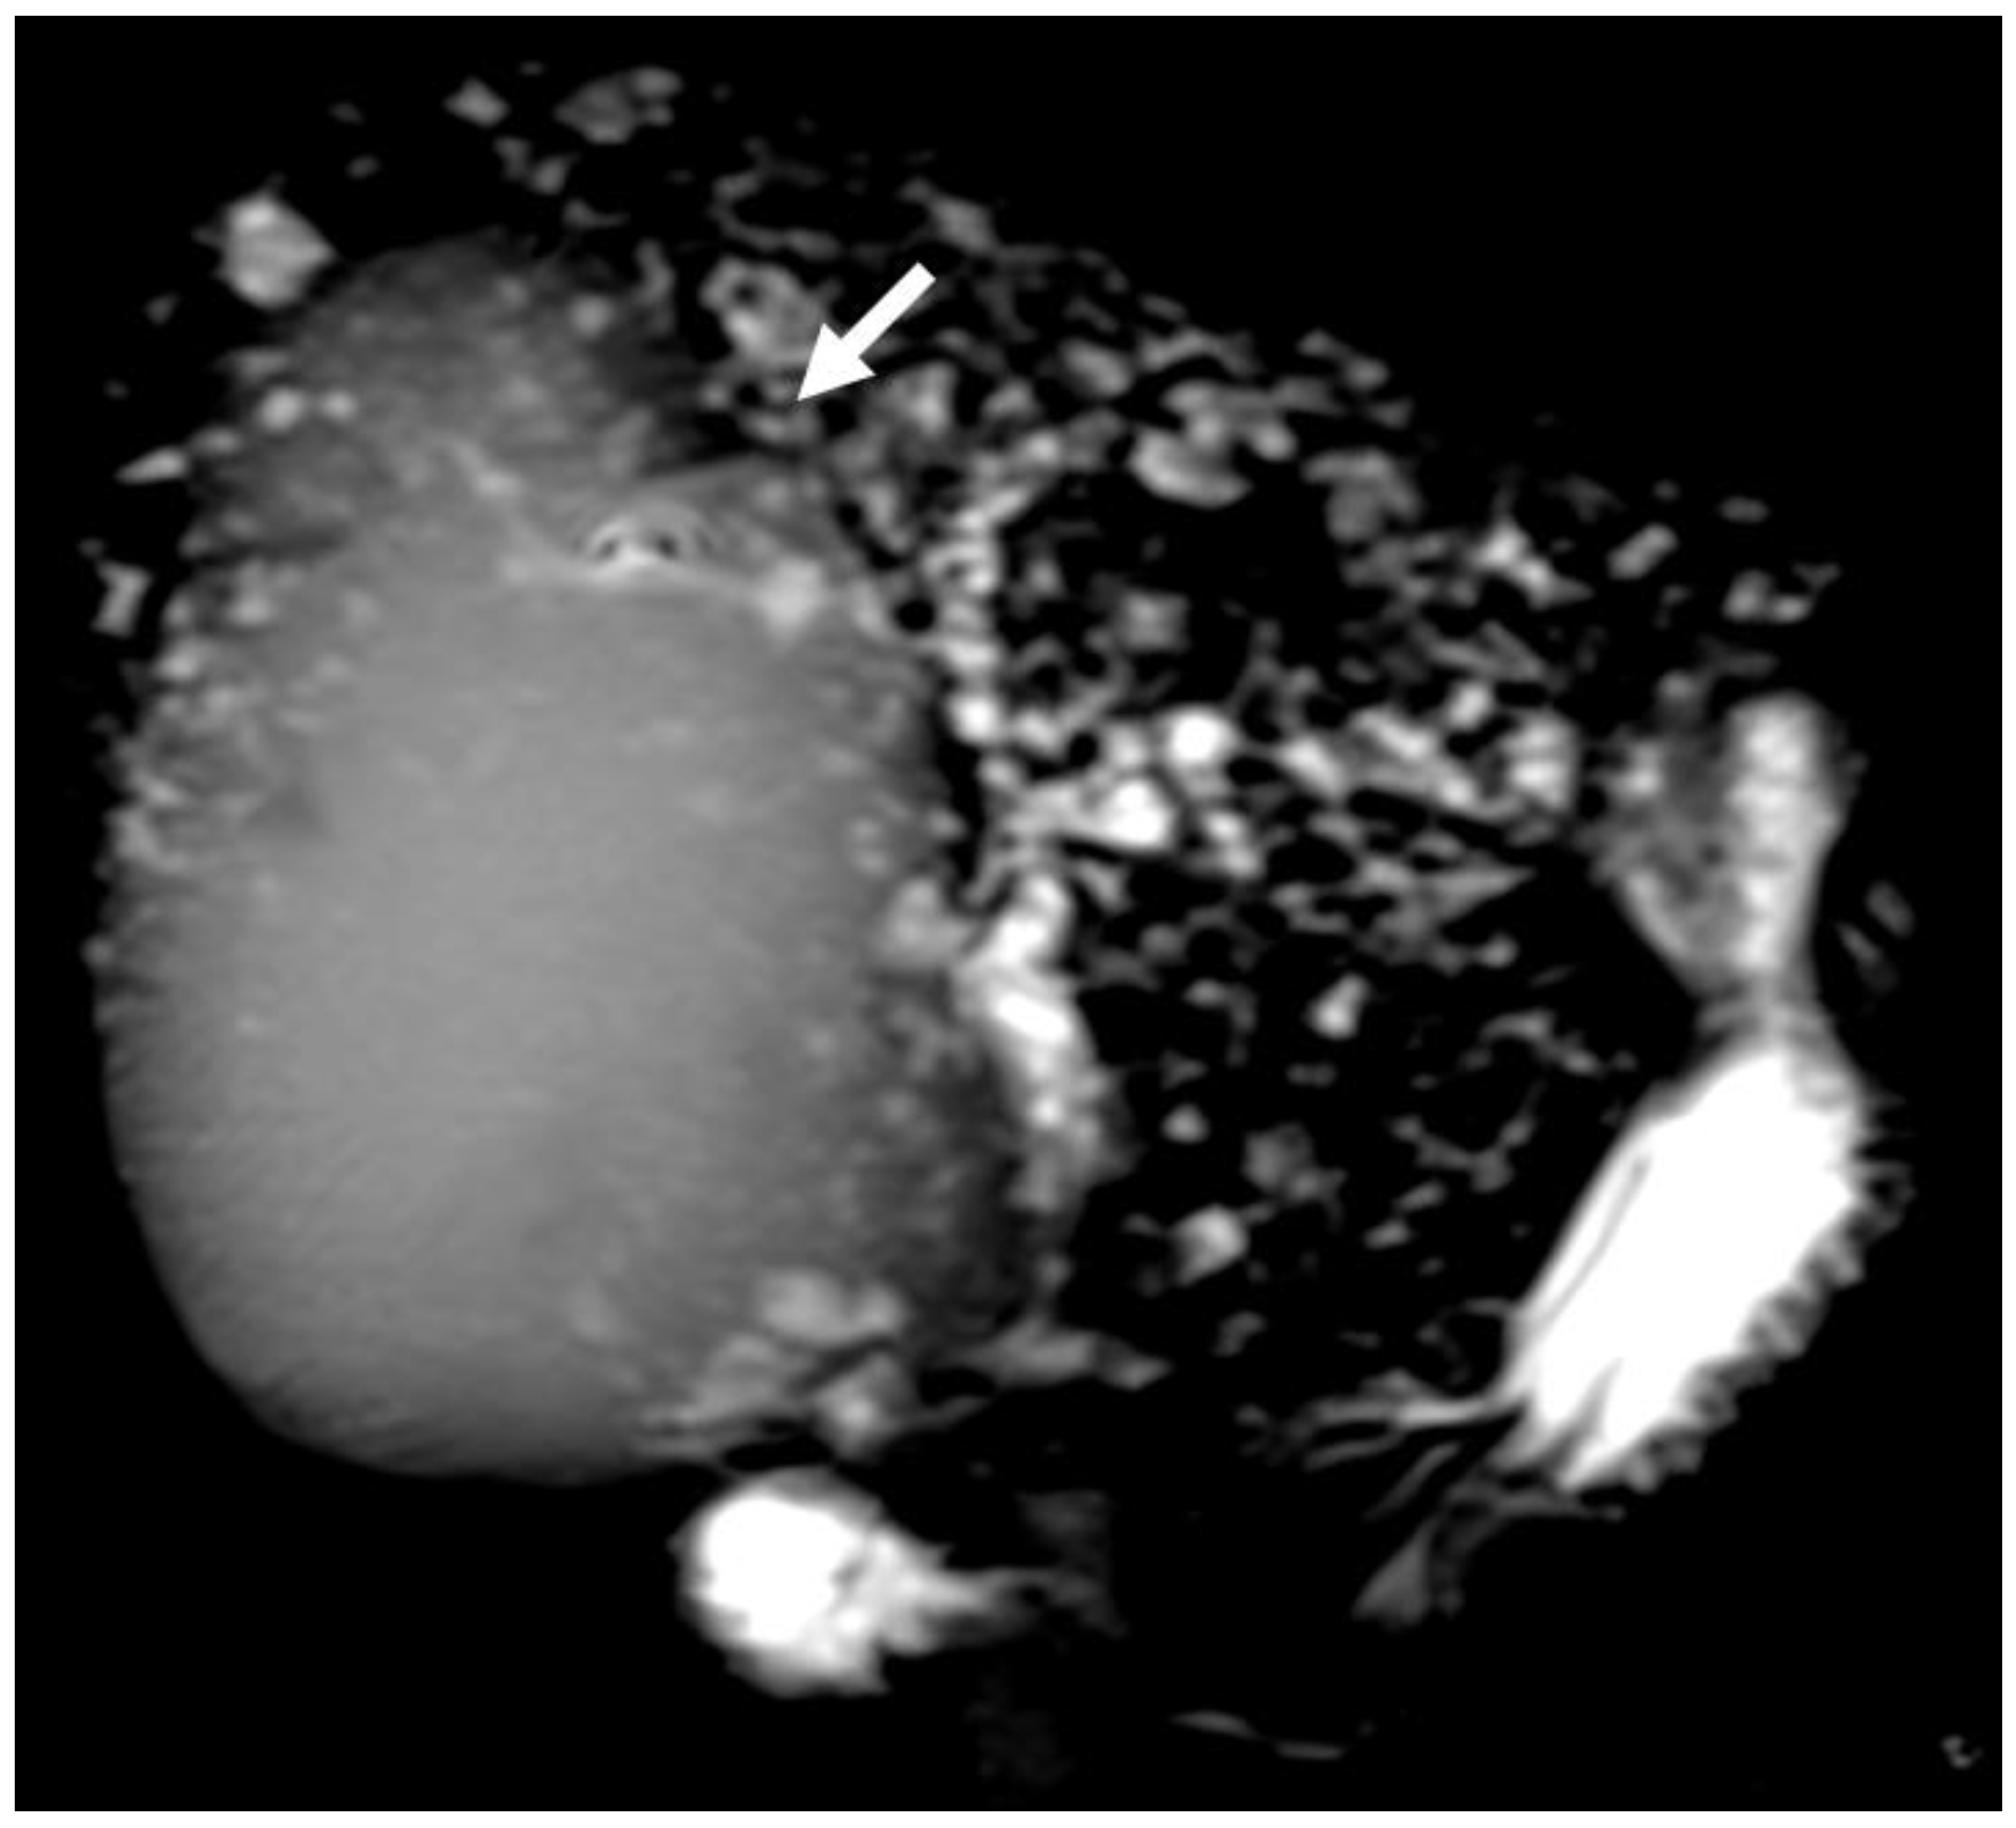

3. Primary Sclerosing Cholangitis

6.2. Intraductal Papillary Neoplasia of the Bile Duct

6.3. Intraductal Tubulopapillary Neoplasms of the Bile Duct

6.4. Hepatobiliary Mucinous Cystic Neoplasm

6.5. Diagnostic Management